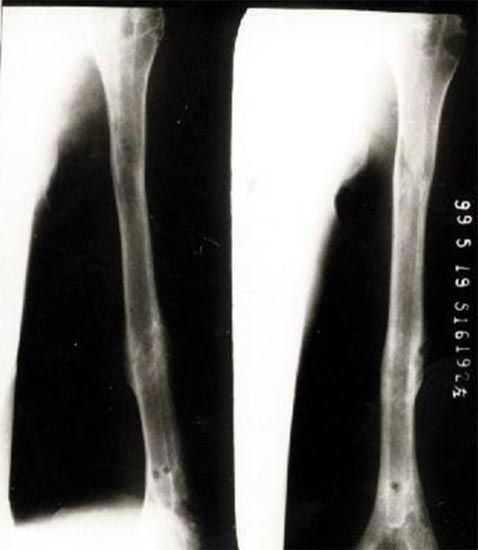

病例一、患者男性,60岁,肱骨远段开放粉碎骨折3年,骨不连,假关节形成。

图1-1我们用钢板固定骨折端提供支撑力,患者自体骨髓细胞经与异体骨和骨生长因子复合,

使没有细胞的植骨材料变成了有细胞的活骨。